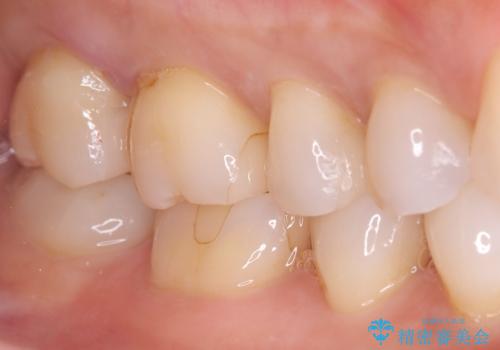

- 昔入れたメタルインレーの下にむし歯が再発したため治療を行った患者様です。

メタルインレーは汚れが付着しやすく、適合も悪いことがあるため、むし歯が再発しやすかったと思われます。

フロスなどの日常の清掃はもちろん不可欠ですが、メタルインレーより汚れが付着しずらいセラミックインレーにて今回は治療を行いました。

セラミックインレー装着時はラバーダムを使用して行っています。